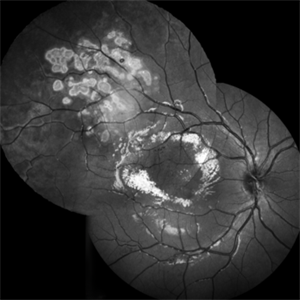

Morbus Coats

Sep 27 2022 by Filip Kecer

Red-free picture of eye with Coats disease and after cryo treatment

Photographer: Filip Kecer, National Institute of Childrens Diseases

Imaging device: Spectralis, Heidelberg Engineering

Condition/keywords: COATS, Coats' disease, Cryopexy, red-free